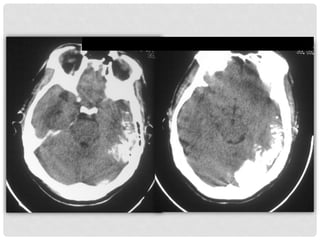

TOMOGRAFIA

COMPUTADA

DE CRANEO

TC

Se corroboran las calcificaciones

intracraneanas, extensas,

unilaterales, con patrón giriforme

en topografía del hemisferio

cerebral izquierdo, de predominio

posterior, en el lóbulo temporal.

CALCIFICACIONES INTRACRANEANAS:

Un aspecto radiográfico común en este síndrome es

la presencia de calcificaciones intracraneales, así

como hemangiomas en la aracnoides y piamadre,

acompañados de atrofia y esclerosis de la corteza

cerebral.